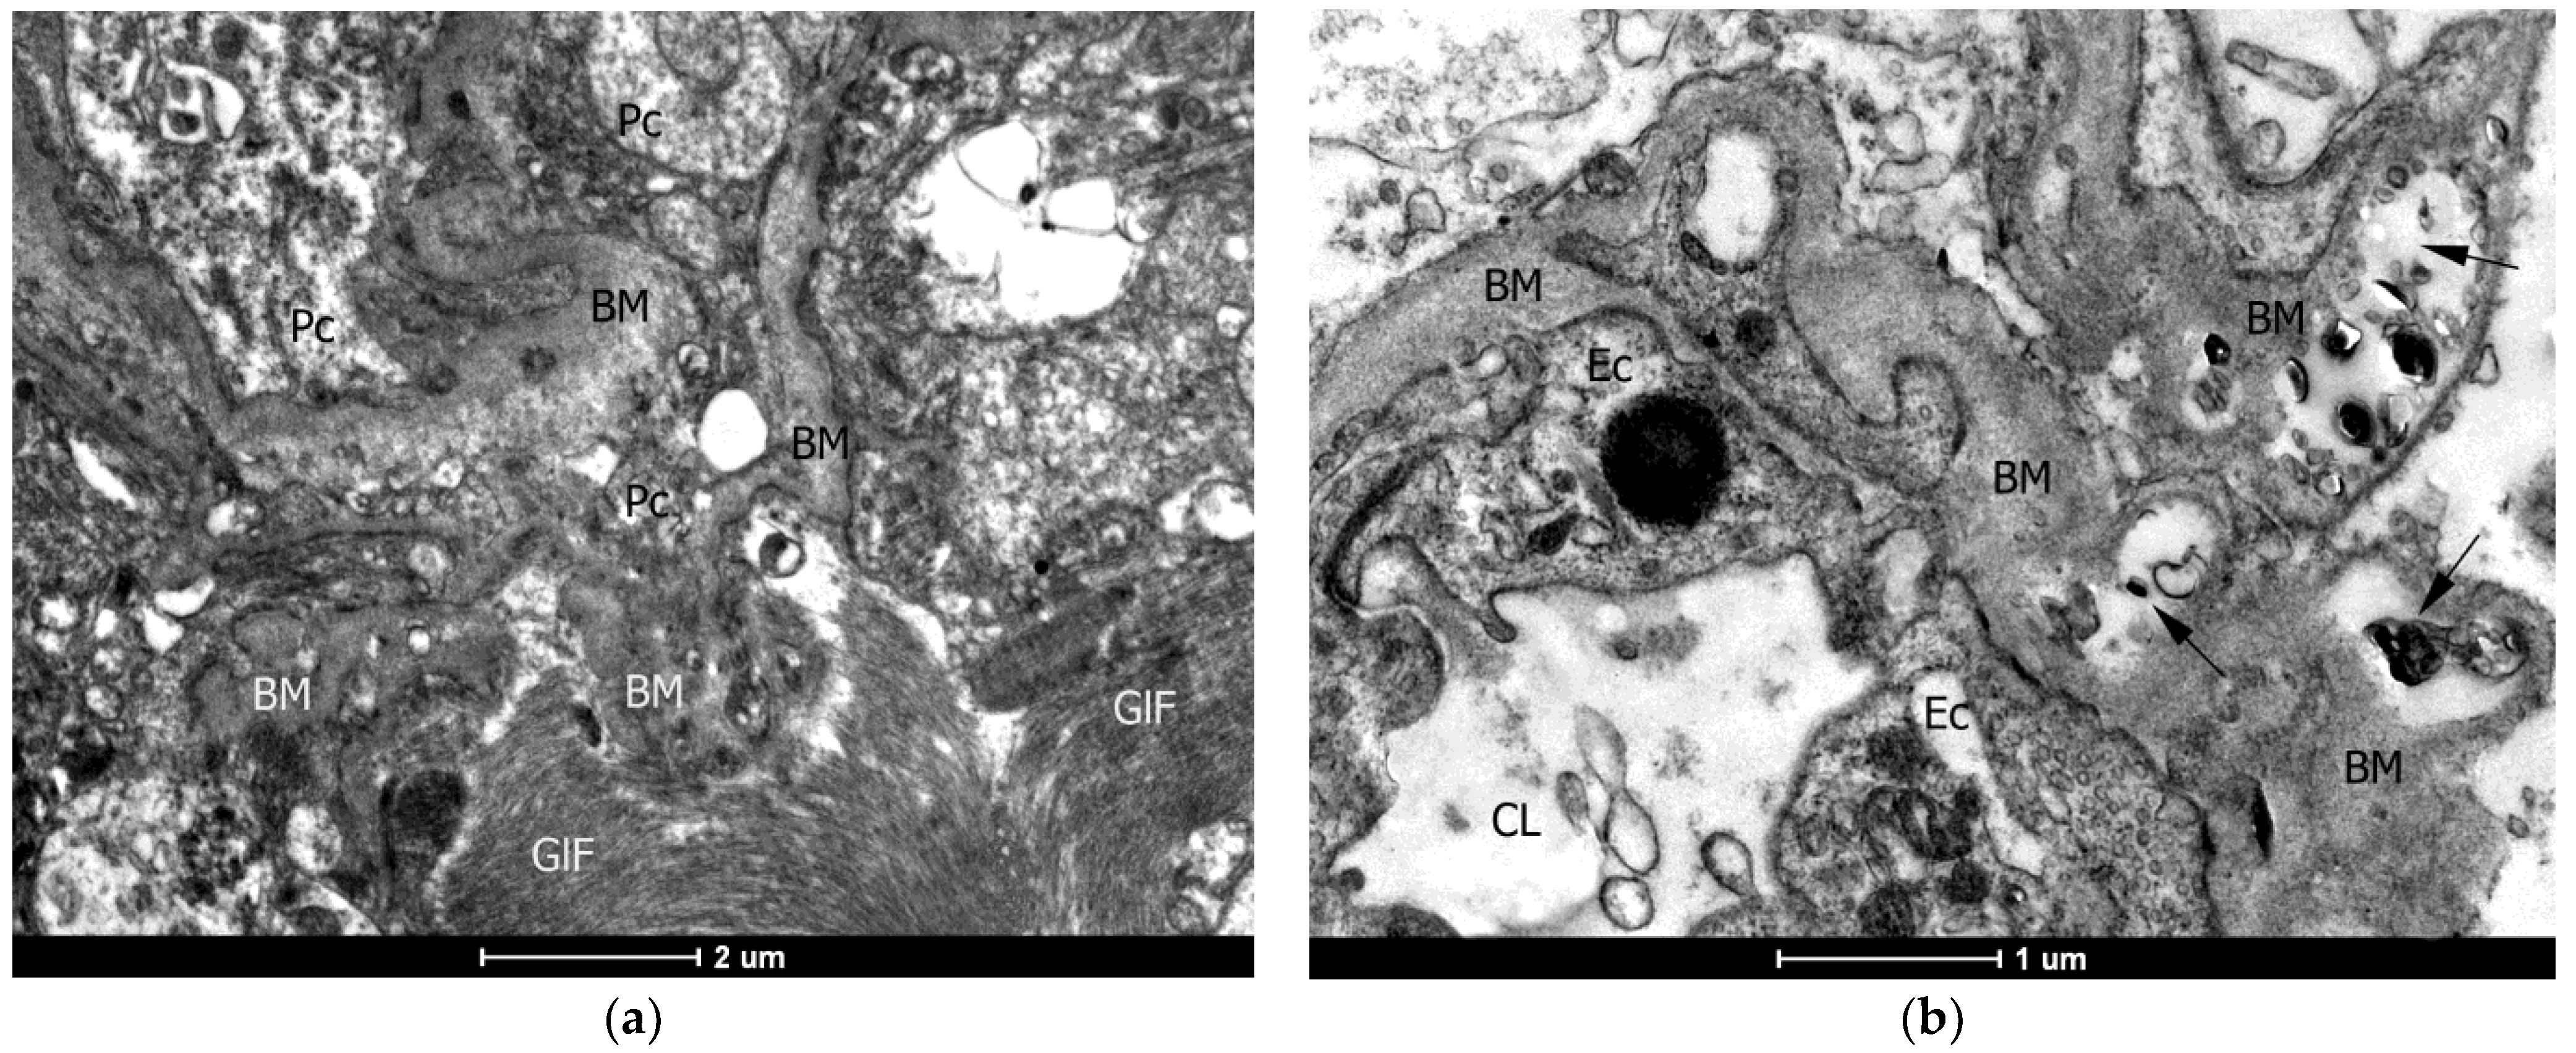

2.4. Ultrastructural (TEM) Examination of the Vascular Wall of the Capillaries

4.2. Transmission Electron Microscopy (TEM)